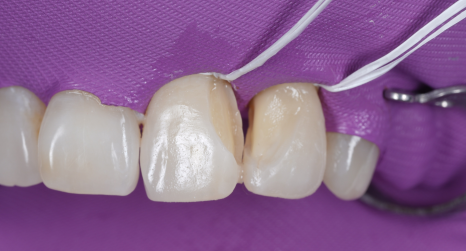

촬영일 : 251230

치아와 레진 사이에 아주 작은 턱이라도 생기지 않도록 매끄럽게 다듬는 데 많은 공을 들였습니다ㅎㅎ

그래야 나중에 환자분이 양치질을 할 때, 치실을 사용할 때 잘 닦여서 세균이 머물 자리가 생기지 않기 때문이죠.

모든 과정을 마치고 환자분께서 "원장님, 이제야 정말 제 치아 같아요. 마음 놓고 크게 웃을 수 있겠어요!"라며 기뻐하시더라고요ㅎㅎ

저 또한 환자분이 겪으셨던 마음고생을 잘 알기에 큰 보람을 느꼈던 순간이었습니다.

주변 치아와 구분이 안 갈 정도로 자연스러운 투명감을 되찾았고 무엇보다 이제는 치실이 부드럽게 통과하며 잇몸을 깨끗하게 관리할 수 있게 되었죠^^